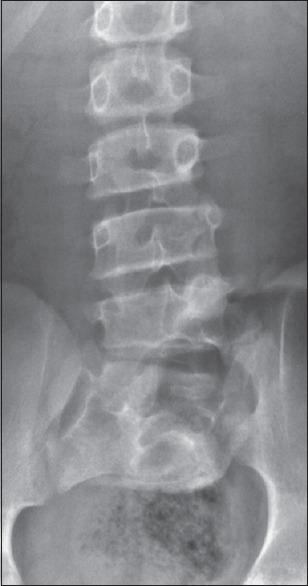

与骶骨发育不全、低位脊髓、脂肪脊髓脊膜膨出和脊髓纵裂畸形相关的Klippel-Feil综合征伴脊髓栓系综合征:神经管缺陷五联征沿整个脊柱轴分布。

Klippel-Feil Syndrome Associated with Sacral Agenesis, Low Lying Cord, Lipomyelomeningocele and Split Cord Malformation Presenting with Tethered Cord Syndrome: Pentads Neural Tube Defects Spread along Whole Spinal Axis.

Neural tube defects are congenital development anomaly of the central nervous system and usually have relatively more predilection to affect at anterior and posterior neuropore embryological development sites, so usually one or two defects are commonly encountered. However, occurrence of simultaneous multiple neural tube defects is very rare, presence of constellation of five neural defects is extremely rare, and all defects add up together to produce gross neurological deficit. We present an interesting case of a 23-year-old male who presented with history of lower backache and noticed wasting and weakness of lower limbs associated with difficulty in walking for the last 2 years but had no associated sphincter disturbances. He was operated for lumbosacral lipomeningocoele repair at the age of 1 year. He was asymptomatic, following the first surgical intervention. At the current admission, he underwent re-exploration of surgical wound with surgical repair although suffered mild-temporary neurological worsening in the immediate postoperative period. Imaging feature and management of such rare constellation of five embryological anomalies and its significance and brief literature are discussed.

神经管缺陷是中枢神经系统的先天性发育异常,通常相对更倾向于影响神经孔前后的胚胎发育部位,所以通常会遇到一两个缺陷。然而,同时出现多个神经管缺陷的情况非常罕见,出现五个神经缺陷的组合极为罕见,所有这些缺陷加在一起会导致严重的神经功能缺损。我们报告了一例有趣的病例,一名23岁男性,有下背部疼痛病史,在过去2年中出现下肢肌肉萎缩和无力,并伴有行走困难,但无括约肌功能障碍。他1岁时接受了腰骶部脂肪瘤性脊膜膨出修补手术。首次手术干预后他无症状。在本次入院时,他接受了手术伤口的再次探查和手术修复,尽管术后立即出现了轻度的暂时性神经功能恶化。本文讨论了这种罕见的五个胚胎异常组合的影像学特征、治疗及其意义,并简要回顾了相关文献。